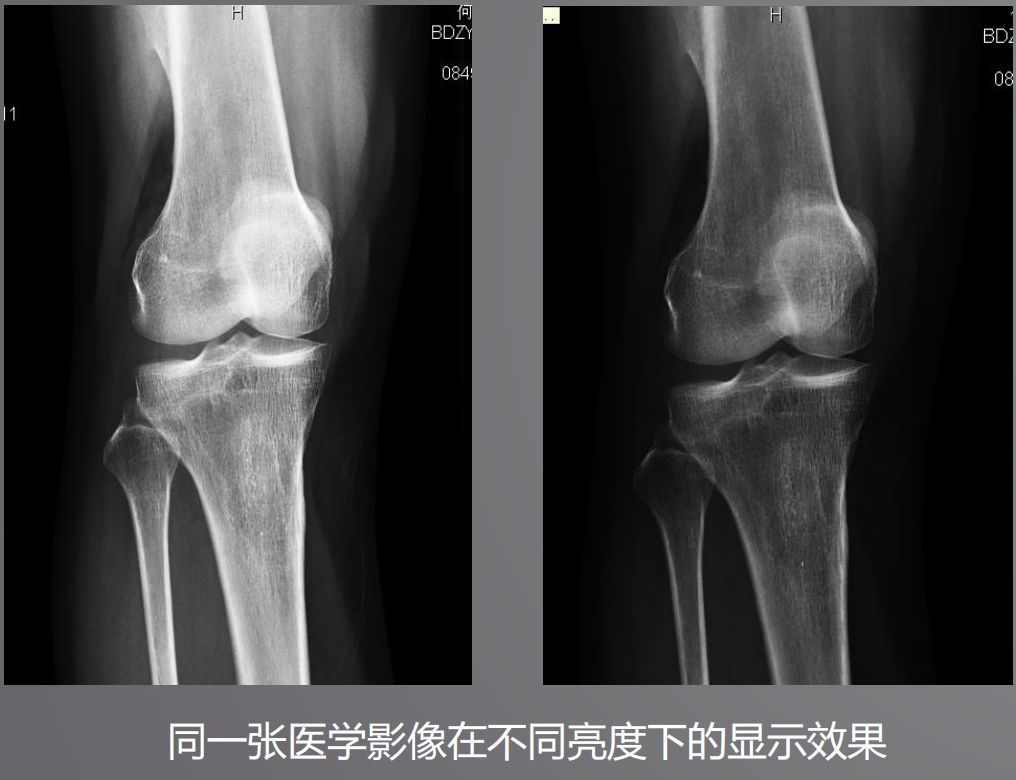

三、高亮度

高亮度從字面上就非常好理解了,回想在傳統(tǒng)膠片時(shí)代,閱片都是直接夾在大大的發(fā)光白板上。而平時(shí)我們?yōu)g覽網(wǎng)頁或者看視頻并不需要那么高的亮度,導(dǎo)致普通顯示器亮度偏低,達(dá)不到醫(yī)用閱片的標(biāo)準(zhǔn)。

根據(jù)DICOM Part14規(guī)定,所有醫(yī)學(xué)顯示器必須符合GSDF的標(biāo)準(zhǔn),確保顯示區(qū)域亮度符合一致性。而普通顯示器是不需要刻意符合這個(gè)標(biāo)準(zhǔn)的。

醫(yī)用顯示器通過系統(tǒng)測(cè)量和調(diào)整每一個(gè)像素的亮度,降低中心和角落之間亮度和色彩的不均勻性,通過減少這些差異,確保顯示器每個(gè)顯示區(qū)都能符合DICOM GSDF標(biāo)準(zhǔn)。